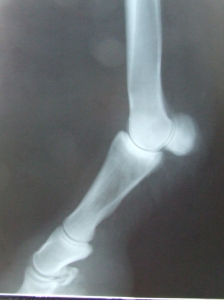

RTG

pravá zadní

levá zadní

pravá přední

levá přední